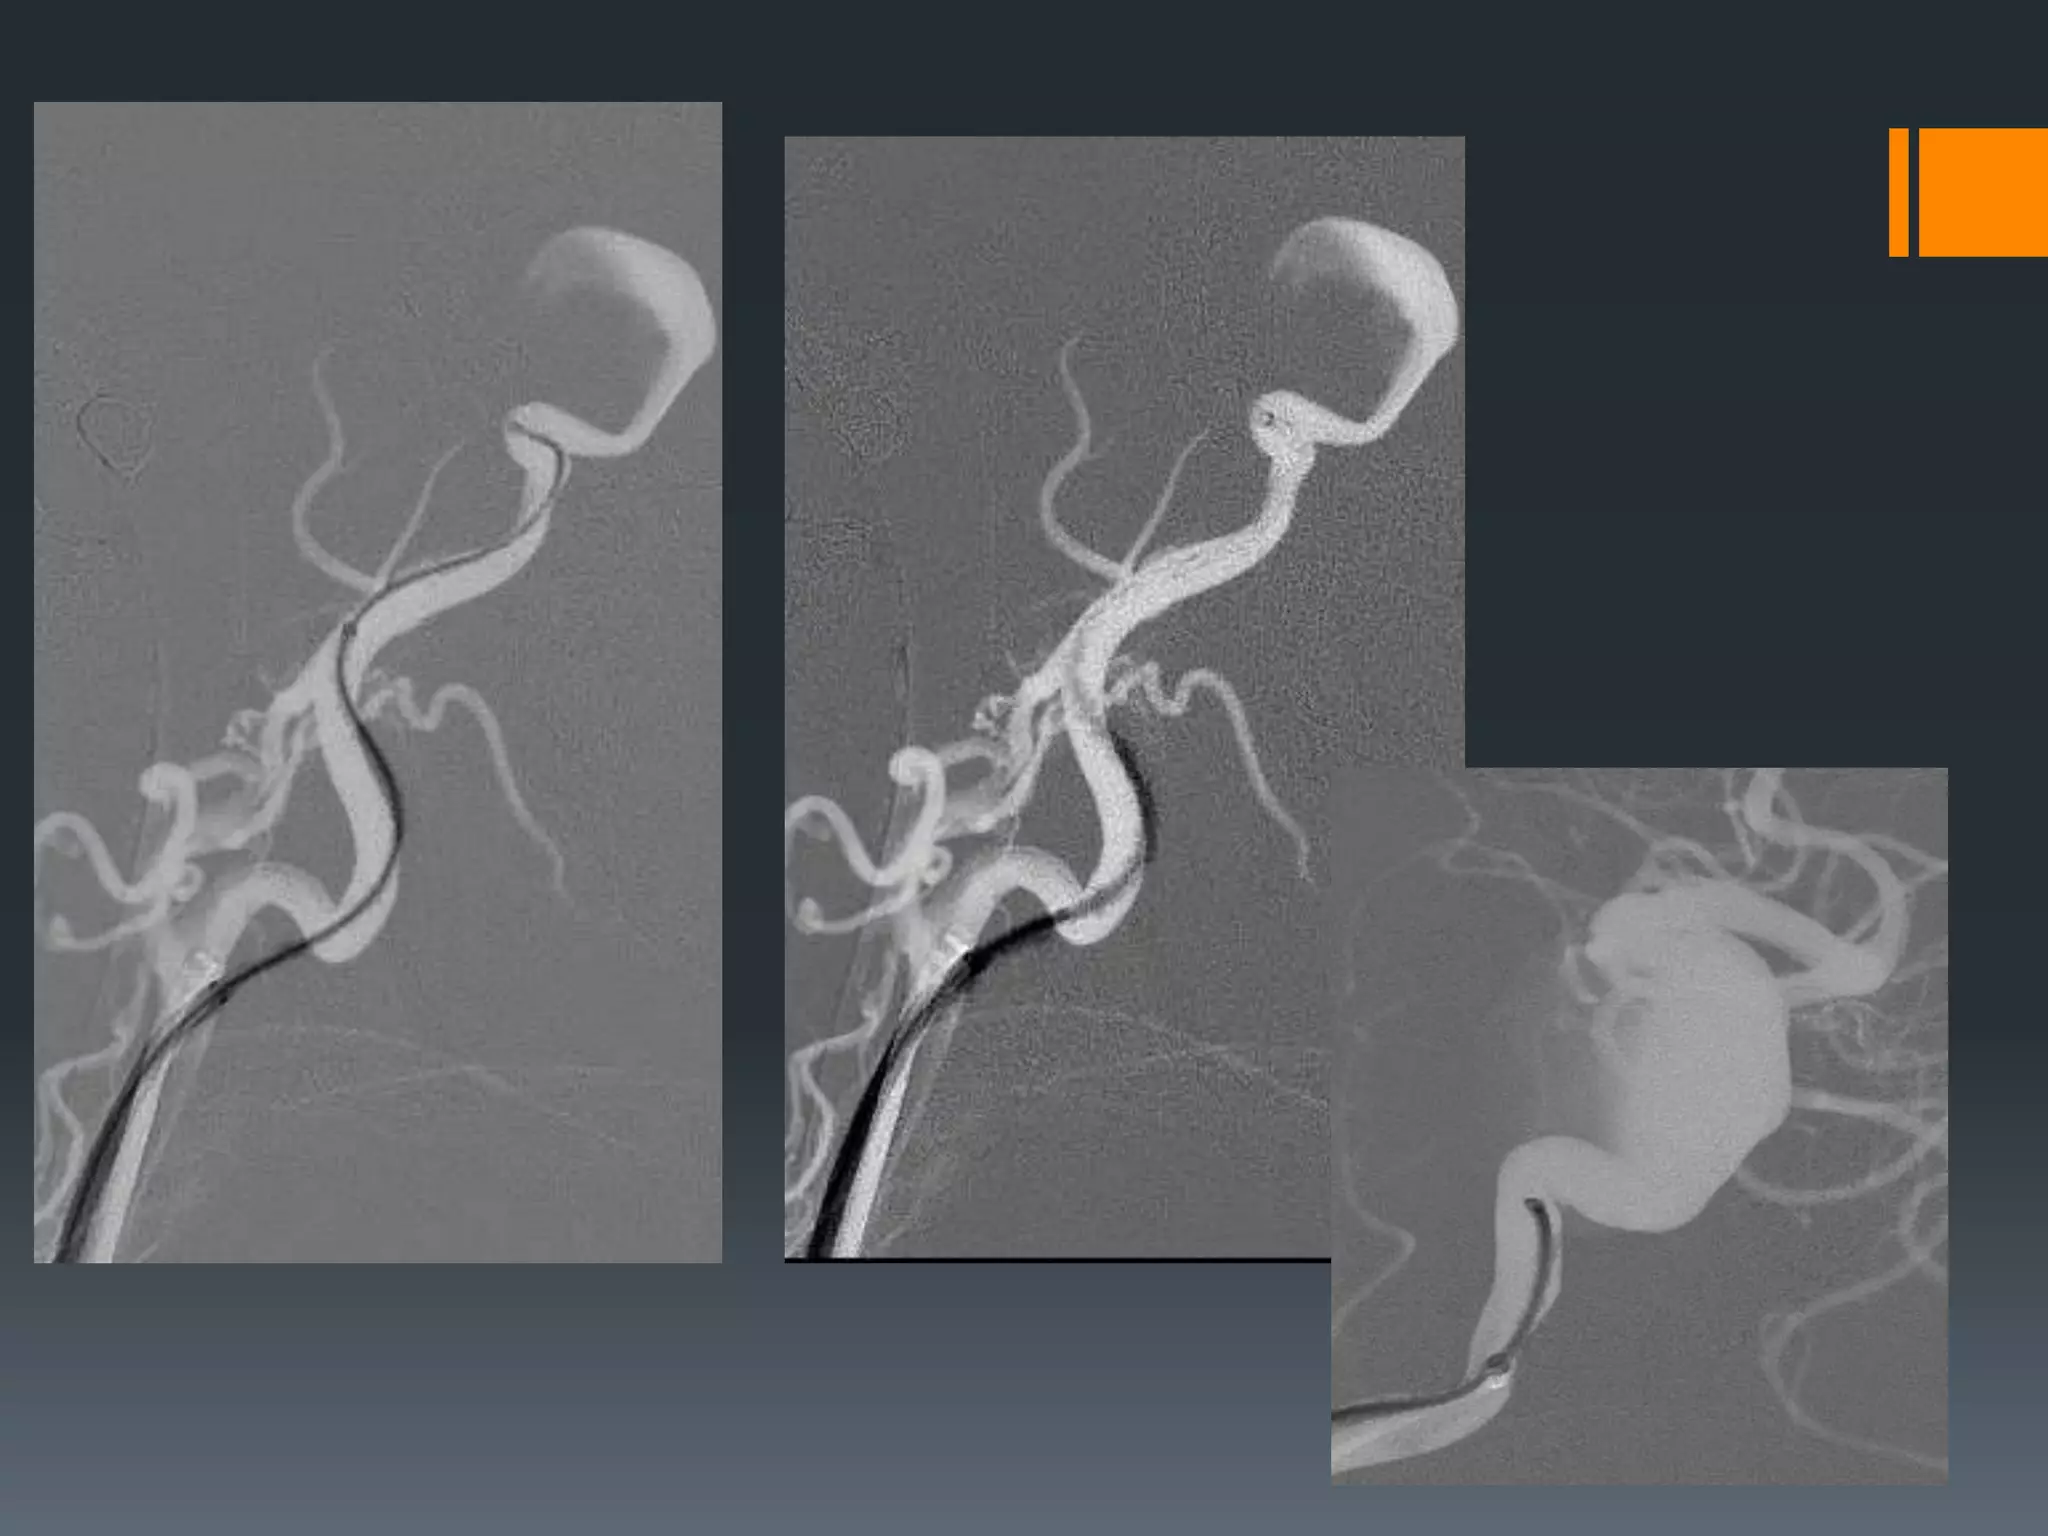

This document discusses tricks and techniques for difficult cannulations during neurointerventional procedures. It outlines strategies for accessing the aortic arch, internal carotid artery (ICA), and areas distal to aneurysms. Long sheaths, distal access catheters, and co-axial techniques are presented as options that have improved cannulation success. Guidance on sheath and catheter selection is provided for different vessel paths. The importance of catheter placement as high as possible in the ICA is emphasized. Reverse curve cannulations are also mentioned. Overall, the document stresses that careful cannulation is critical for procedural success and different strategies may be needed depending on the vessel target.